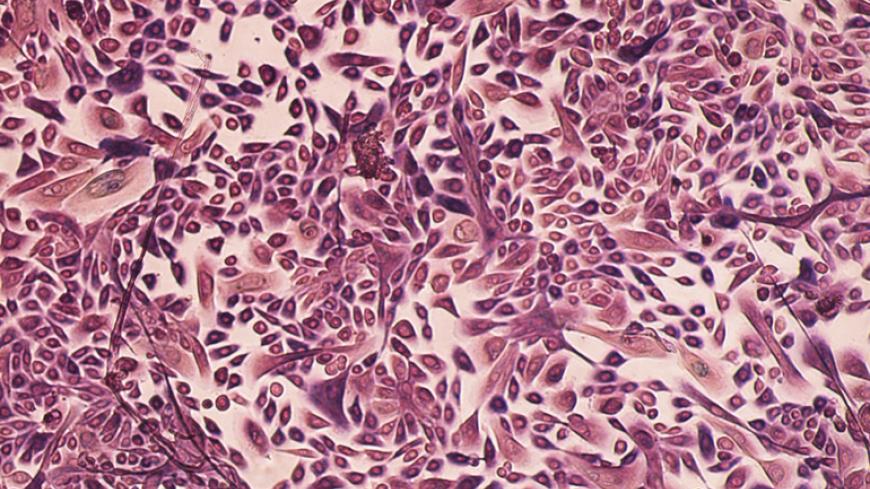

Визначальну роль у постановці точного діагнозу матимуть результати біопсії, адже тільки у лабораторних умовах за допомогою мікроскопу можна вивчити особливості клітин та тканин новоутворення. До речі, при виконанні біопсії також застосовується УЗД – для контролю точності маніпуляції (лікар бачить, звідки саме береться зразок, тому суттєво підвищується ефективність діагностики).

Рак молочних залоз може виглядати по-різному, адже існує багато його видів. Пухлини мають різний розмір та форму, характер контурів, розташування тощо. Часто злоякісні новоутворення виглядають на УЗД як темні плями з нечіткими краями, що розходяться у вигляді променів. Проте наявність цих ознак не дає можливості зробити однозначний висновок, потрібна біопсія.